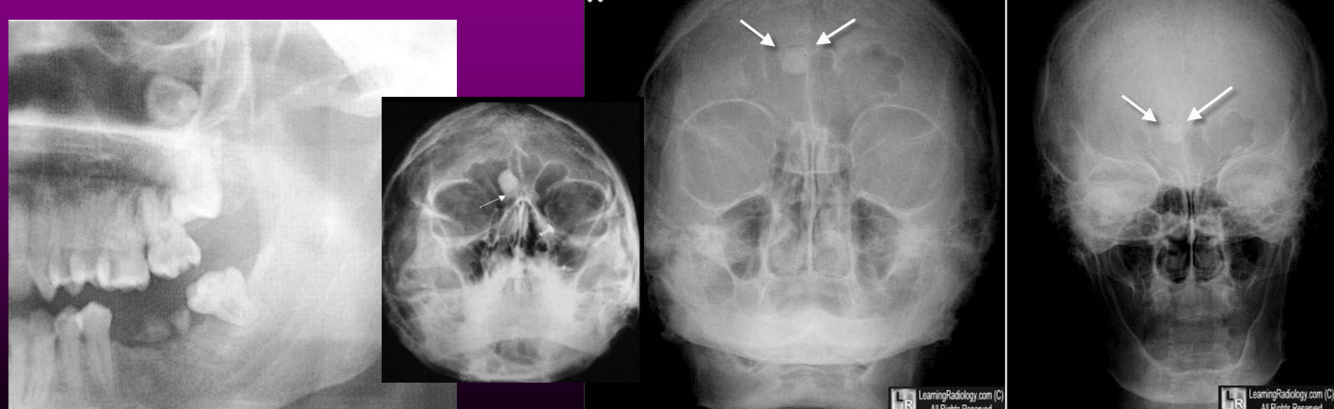

• São mais comuns que as lesões gnáticas.

Geralmente assintomáticos. Sintomas como sinusite, rinorréia, podem invadir a órbita e causar proptose, diplopia e diminuição da acuidade visual.

• Seio frontal é o mais envolvido, seguido pelo etmoidal e maxilar